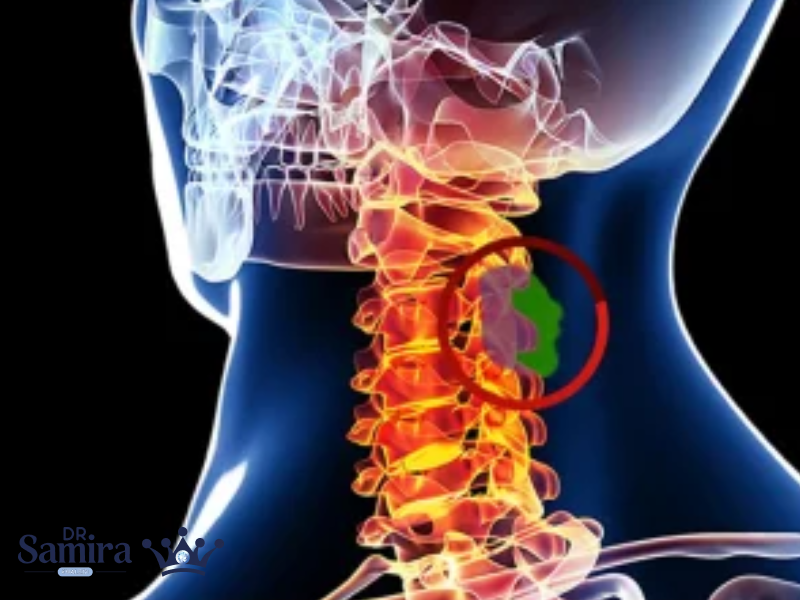

کیست آراکنوئید مغز نوعی حفره پر از مایع مغزی ـ نخاعی است که بین لایههای پرده...